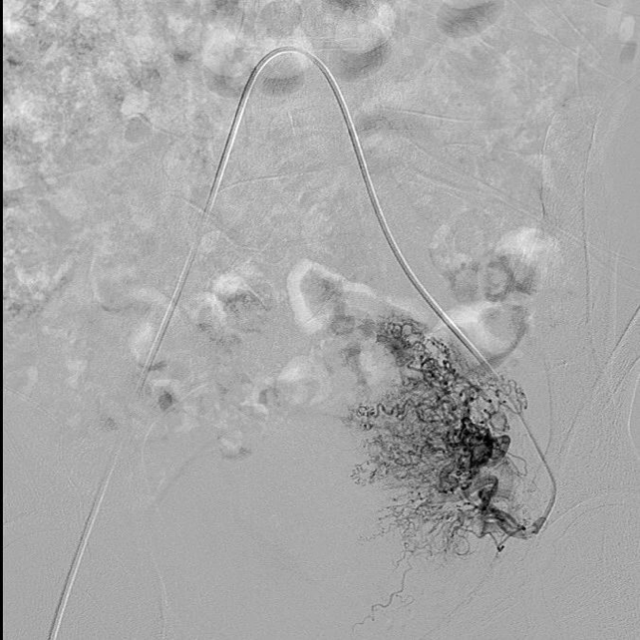

为患者行子宫动脉栓塞术中

在制定出周密治疗方案后,妇科专家向患者及家属详细告知了病情,手术正式开始。由医学影像科做完子宫动脉栓塞术后,妇科专家继续为患者进行腹腔镜子宫瘢痕妊娠清除术,手术过程「干净利落」,出血量仅 10 ml。术后 4 天,患者就痊愈出院。

子宫动脉栓塞术前,子宫动脉血运非常丰富

子宫动脉栓塞术后,栓塞剂暂时阻断了动脉血流

据昆明同仁医院医学影像科宋光义主任介绍,双侧子宫动脉栓塞术,就是通过介入手段,栓塞子宫两侧动脉,迅速达到减少宫腔内出血的目的,被认为是目前可以取代子宫切除治疗大出血的技术之一。用做栓塞剂的明胶海绵,一方面可迅速阻断血流,减少大出血的发生;另一方面,海绵经过几天时间即可被身体吸收使血管再通,避免了对正常子宫血供的影响。